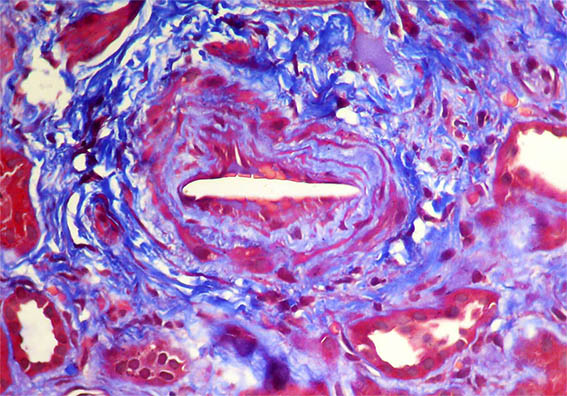

Figura 7. Tricrómico de Masson, X200. Observe la luz de la arteria.